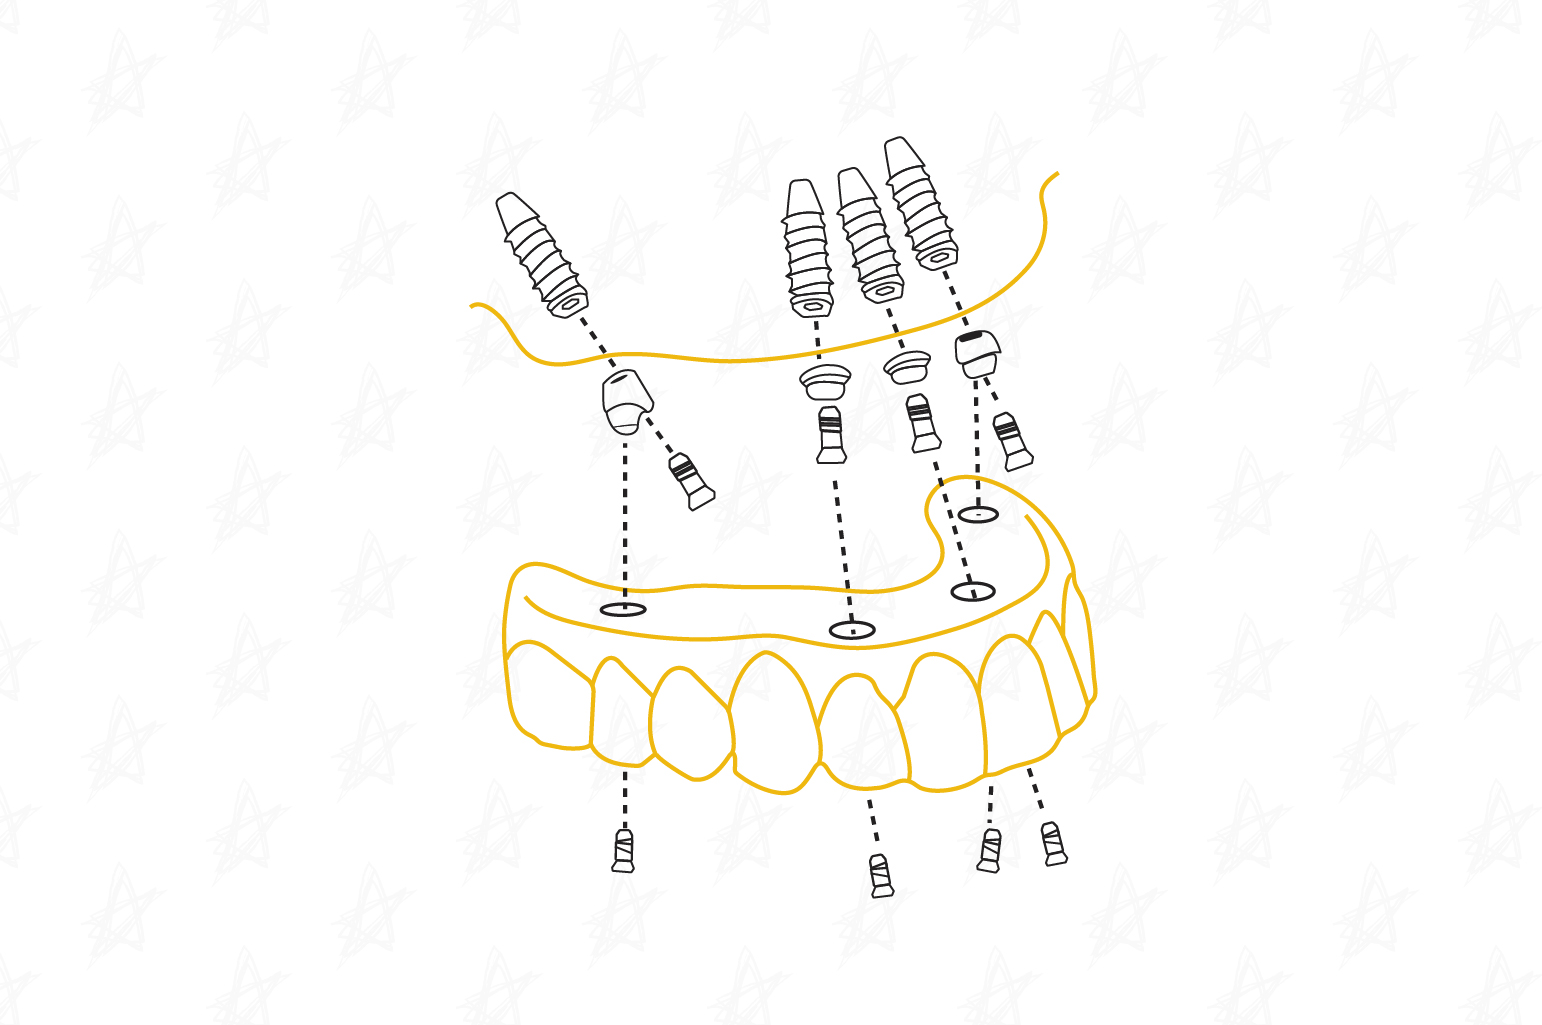

All-on 4 / All -on-6 Full Mouth Restoration

Key Benefits:

- Natural-looking fixed teeth

- Immediate improvement in chewing and speech

- Greater stability and comfort

- Helps preserve bone and facial structure

- Faster and more efficient treatment than traditional implants

All-on-4 and All-on-6 treatments are advanced oral rehabilitation solutions designed for patients who have lost most or all of their teeth. They involve the strategic placement of 4 or 6 dental implants that serve as the foundation for a full-arch fixed prosthesis, restoring function, aesthetics, and stability in a single smile.

These procedures allow for the replacement of a full set of teeth with fixed prostheses, eliminating the need for removable dentures. In many cases, temporary teeth can be placed the same day, allowing the patient to leave the clinic with a renewed smile.